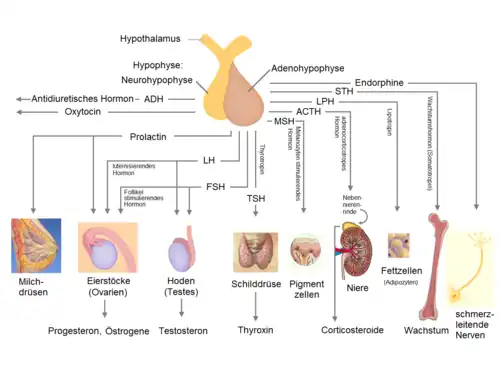

Die Hypophyse ist mit dem Hypothalamus über den Hypophysenstiel (Infundibulum) verbunden und wird in

eingeteilt. Entwicklungsgeschichtlich und funktionell unterscheiden sich die Hypophysenlappen voneinander. Während die Adenohypophyse aus einer Ausstülpung des Rachendaches, der sogenannten Rathke-Tasche, hervorgeht und sich der Neurohypophyse anlagert, ist die Neurohypophyse eine Ausstülpung des Zwischenhirns. Dieser Unterschied ist histologisch[2] zu erkennen, denn während in der Adenohypophyse verschiedene in Ballen angeordnete endokrine Drüsenzellen vorkommen, dominieren in der Neurohypophyse vor allem Nervenzellfortsätze, sogenannte Axone, deren Zellkörper im Hypothalamus liegen. Somit vermag die Adenohypophyse Hormone unter Kontrolle des Hypothalamus selbst zu bilden und die Neurohypophyse ist hingegen als Speicher- und Sekretionsorgan für die im Hypothalamus gebildeten Hormone zuständig. Aus Epithelresten des Stiels der Rathke-Tasche kann zusätzliches Vorderlappengewebe entstehen, das als Rachendachhypophyse bezeichnet wird.[3]

Unterschieden werden Hormone, die direkt auf ihre Zielorgane einwirken (nichtglandotrope Hormone), und solche, welche die Hormonproduktion nachgelagerter endokriner Drüsen stimulieren (glandotrope Hormone). Die glandotropen Hormone werden auch Steuerungshormone genannt, da sie die Funktion anderer Hormondrüsen regulieren.[4] Direkt auf ihre Zielorgane wirken das Wachstumshormon Somatotropin (STH für somatotropes Hormon bzw. GH für growth hormone) sowie Prolactin. Bei den glandotropen Hormonen werden die auf die Keimdrüsen (Gonaden) wirkenden gonadotropen Hormone follikelstimulierendes Hormon (FSH) und Luteinisierendes Hormon (LH) sowie die nichtgonadotropen Hormone, nämlich das die Nebennierenrinde stimulierende adrenocorticotrope Hormon (ACTH) und das die Schilddrüse stimulierende Thyroideastimulierende Hormon (TSH) unterschieden. Durch Prozessierung eines größeren Vorläuferpeptides, des Proopiomelanocortins, entstehen neben dem ACTH zudem Melanotropin (MSH), β-Endorphin und met-Enkephalin. Die Hormonproduktion der Hypophyse wird mittels Liberinen und Statinen durch den Hypothalamus geregelt.

Hormone des Hypophysenzwischenlappens

Der Hypophysenzwischenlappen ist unter anderem Bildungsort der Melanozyten-stimulierenden Hormone (MSH, Melanotropine).

Hormone des Hypophysenhinterlappens (Neurohypophyse)

Bei den Hormonen, die im Hypophysenhinterlappen gespeichert und ausgeschüttet werden, handelt es sich um das Oxytocin sowie das antidiuretische Hormon (ADH), das auch als Adiuretin oder Vasopressin bezeichnet wird. ADH wird im Nucleus supraopticus (Kerngebiet, das sich oberhalb des Sehnerven befindet), Oxytocin im Nucleus paraventricularis (Kerngebiet im Hypothalamus) des Hypothalamus gebildet.